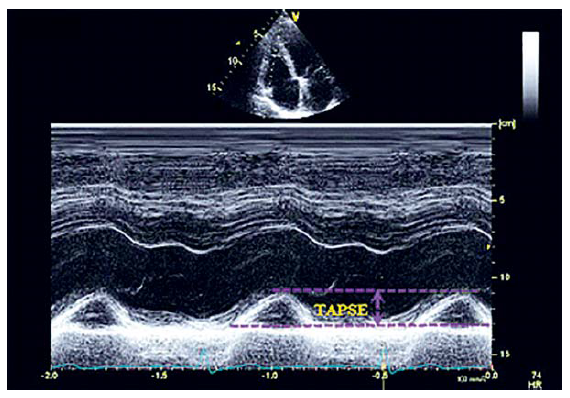

Оценка систолической функции может быть проведена с помощью измерения TAPSE в М-режиме.

Измерение TAPSE является простой, менее зависимой от качества изображения, легко воспроизводимой методикой, не требует сложного оборудования или длительного анализа изображений. Однако оценка TAPSE предполагает, что сдвиг одного сегмента представляет функцию сложной трехмерной структуры ПЖ, что не является вполне правомерным.

Согласно международным рекомендациям, методика оценки TAPSE должна использоваться в повседневной практике как простая методика оценки функции ПЖ с нижней границей для систолической функции ПЖ равной 17 мм (рис. 11).

Рис. 11. Измерение TAPSEв М-режиме